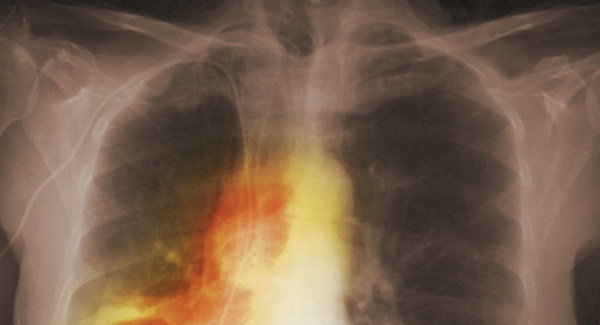

Almost 160 people a day are diagnosed with cancer in Ireland, that’s one person every ten minutes, or more than 57,000 people a year.

The Irish Cancer Society today launched a new hard hitting campaign telling people to ‘Get’ Cancer, which aims to get people talking about the disease.